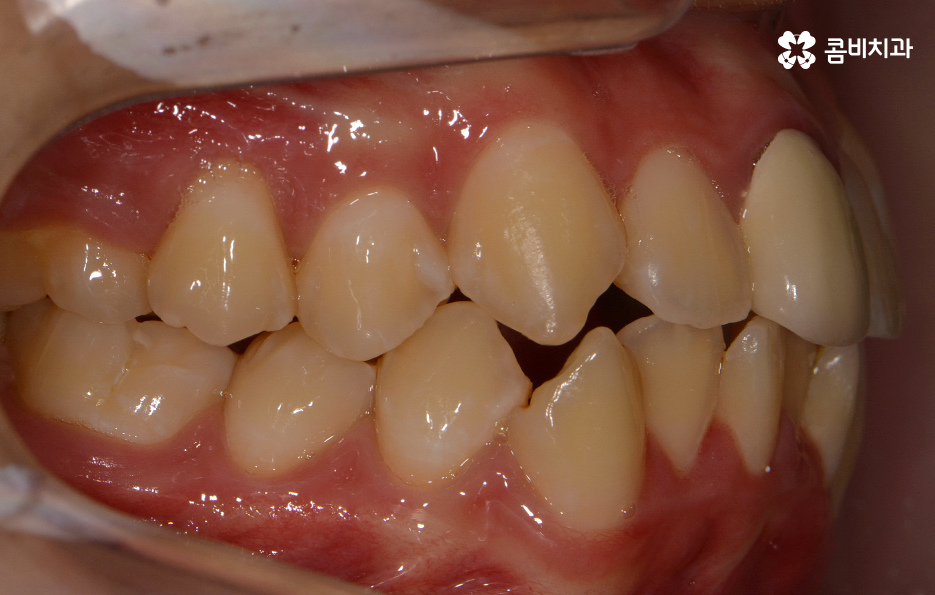

덧니는 치아가 제대로 자리를 잡지 못하여 발생하게

되는 경우라고 할 수 있는데 턱이 작거나 치아가 큰 경우 치아가

정상적으로 나올 공간이 부족하여 생기는 경우가 일반적이라고 할 수 있어요.

위 환자분의 케이스는 아랫니에 치아 2개를 발치하여

치아의 이동 공간을 확보하였고 발치교정이 진행될 때는

윗니와 아랫니 각각 2개씩 발치를 하는 경우가 많지만

위 사례는 치열, 교합 등을 고려할 때 아랫니 2개만

발치가 진행되었던 경우라고 볼 수 있어요.